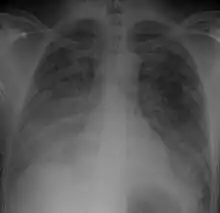

| Chest Xray of a 40 yr old male in acute respiratory distress syndrome as a complication of murine typhus | |